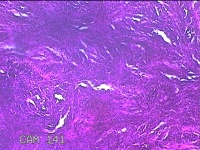

臀部肿物

性别

女

年龄

32岁

临床诊断

脂溢性角化病;皮肤感染

一般病史

颈部臀部丘疹数年。

标本名称

大体所见

灰白粉红色带皮肤样肿物1.8x0.5x0.2cm一个,表面糜烂。